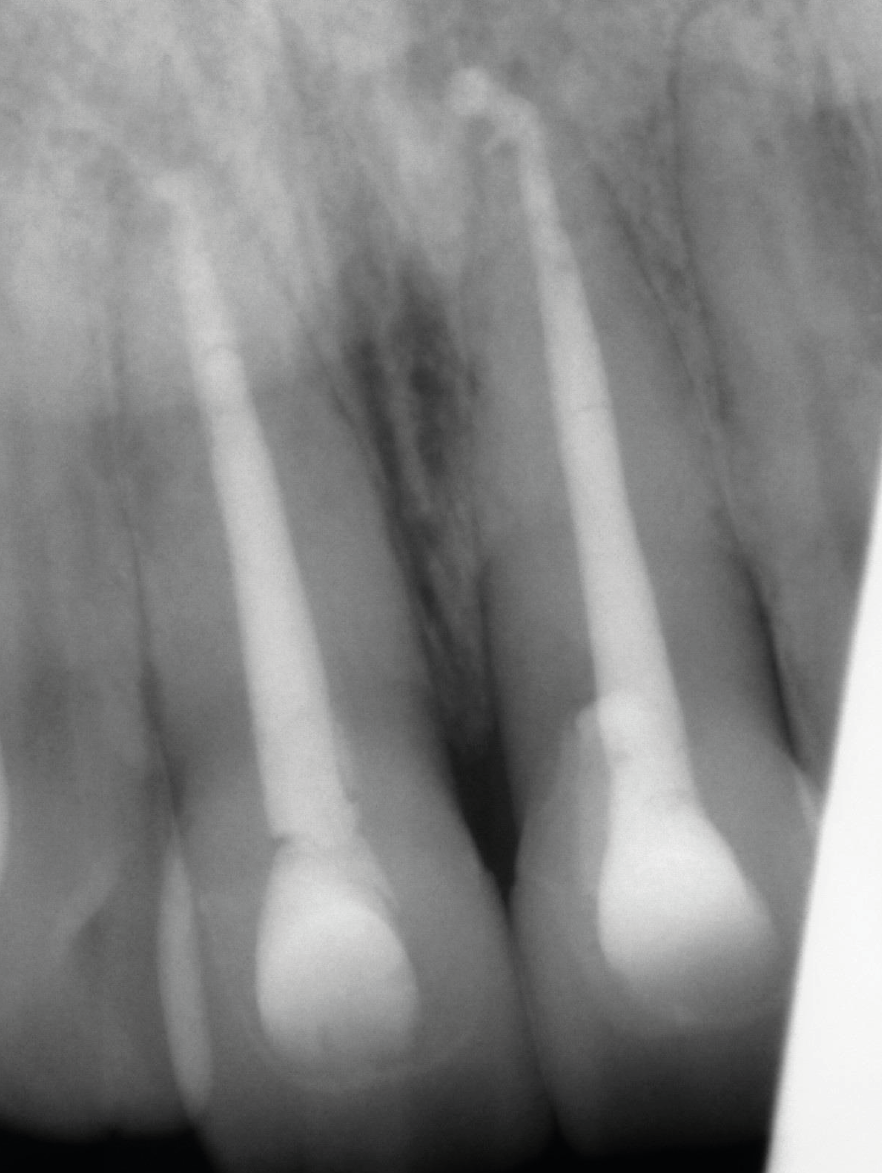

Periapical radiograph with gutta-percha cone in sinus and large periapical area at UR1 and UL1.

Obturation with MTA plug and gutta percha back fill at UR1 and UL1.

12-month review, radiograph  showing reduction in size of periapical areas at UR1 and UL1.